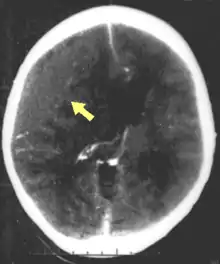

Hematomas, also focal lesions, are collections of blood in or around the brain that can result from hemorrhage.[10] Intracerebral hemorrhage, with bleeding in the brain tissue itself, is an intra-axial lesion. Extra-axial lesions include epidural hematoma, subdural hematoma, subarachnoid hemorrhage, and intraventricular hemorrhage.[38] Epidural hematoma involves bleeding into the area between the skull and the dura mater, the outermost of the three membranes surrounding the brain.[10] In subdural hematoma, bleeding occurs between the dura and the arachnoid mater.[22] Subarachnoid hemorrhage involves bleeding into the space between the arachnoid membrane and the pia mater.[22] Intraventricular hemorrhage occurs when there is bleeding in the ventricles.[38]